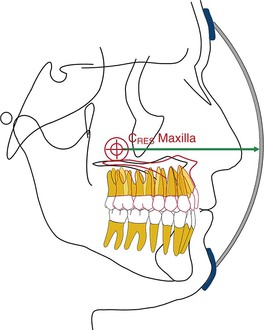

By changing the point of force attachment on the facemask or outer bow of the headgear, the vertical dimension of the face can be very nicely controlled. This is especially important in Class III patients with a long vertical dimension and a steep mandibular plane. Similarly, in Class III patients with a flat mandibular plane and a deep bite, a force below the level of the occlusal plane may be more desirable to rotate the mandible downward and backward (see Fig. 16-10). A line of force closer to the center of resistance of the midface will deliver a translatory force (Fig. 16-11) and a line of force closer to the occlusal plane has a rotational force (Fig. 16-12).

Figure 16-11 Schematic representation of a line of force through the center of resistance (CRES) of the maxilla, which will result in a translatory movement of the maxilla. The precise location of the CRES of the midfacial bones is difficult to locate but most studies point to the area 5- to 10-mm below the orbitale.